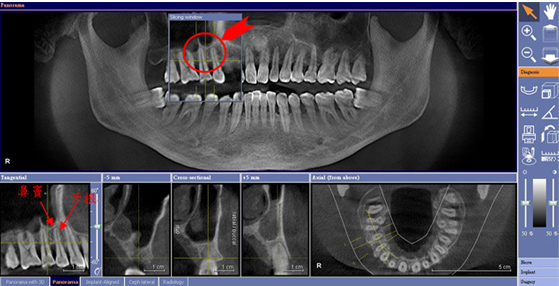

本院新引進德國西門子3D數位電腦斷層掃瞄儀「GALILEOS 3D」,為患者的健康把關。電腦斷層又稱 CT,為 Computerized Tomography 的縮寫,意指經過電腦的處理所現出來的影像「電腦斷層攝影術」。

透過電腦斷層,可以進一步瞭解患者的口腔狀況;進而為植牙手術,乃至其他分科治療,做更妥善的準備。包括︰患者是否罹患牙周疾病、有沒有埋伏智齒、牙齒根管治療(抽神經)的狀況,乃至於瞭解患者下齒槽神經叢的走向,選擇適當長度的植體進行植牙,避免肇生壓迫到神經管或根尖骨頭穿孔的後遺症,對患者的安全做妥適的保護。

簡言之,透過電腦斷層,將可清楚瞭解患者的口內3D狀況、骨質密度、神經走向,以及與上顎鼻竇的距離,這是傳統平面X光所做不到的。本院所引進的「GALILEOS 3D」,拍攝時間僅需14秒。不但是植牙醫師植牙時的優越參考輔助,也能更清楚地向患者做手術方面的說明。為醫病雙方的權益,做更為妥善的把關。

●透過3D影像,可有效測量牙根與上顎鼻竇的正確距離,避免打穿。

主要的關鍵是,3D數位電腦斷層所建構而成的立體成像,比起傳統的平面X光片,在方位判讀上更為精準。臨床實務上,植牙手術很重要的是瞭解解患者齒槽骨內神經管的確切位置,及骨質密度是否可以接受植牙。